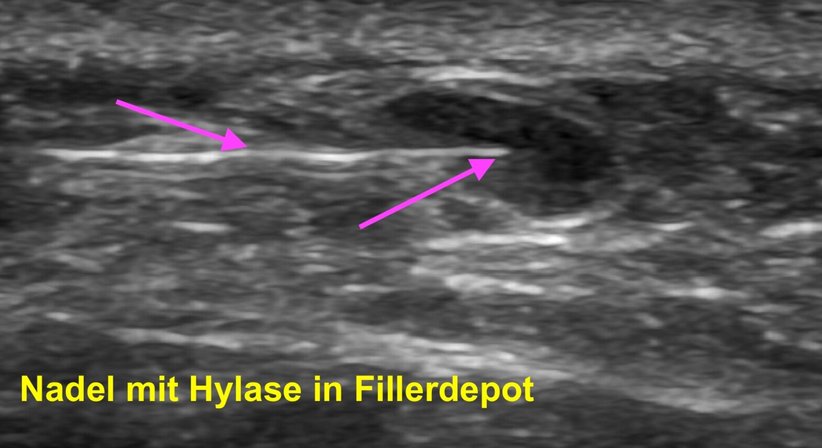

Da Hyaluronsäure-Filler-Depots mit dem hochauflösenden Ultraschall gut sichtbar sind, kann ich diese punktgenau anzielen. Mit einer sehr feinen Nadel injiziere ich Hylase unter Ultraschallkontrolle direkt in das Hyaluronsäuredepot. Innerhalb weniger Stunden beginnt sich die Hyaluronsäure aufzulösen. Je nach Bereich kann der Einstich etwas schmerzhaft sein bzw. kann es zu kurzfristigen Schwellungen kommen. Erfahrung ist bei dieser Behandlung besonders wichtig, da Hylase alle Arten von Hyaluronsäure, einschließlich der körpereigenen, auflöst. Daher müssen Dosierung und genaue Anwendung sorgfältig festgelegt werden.